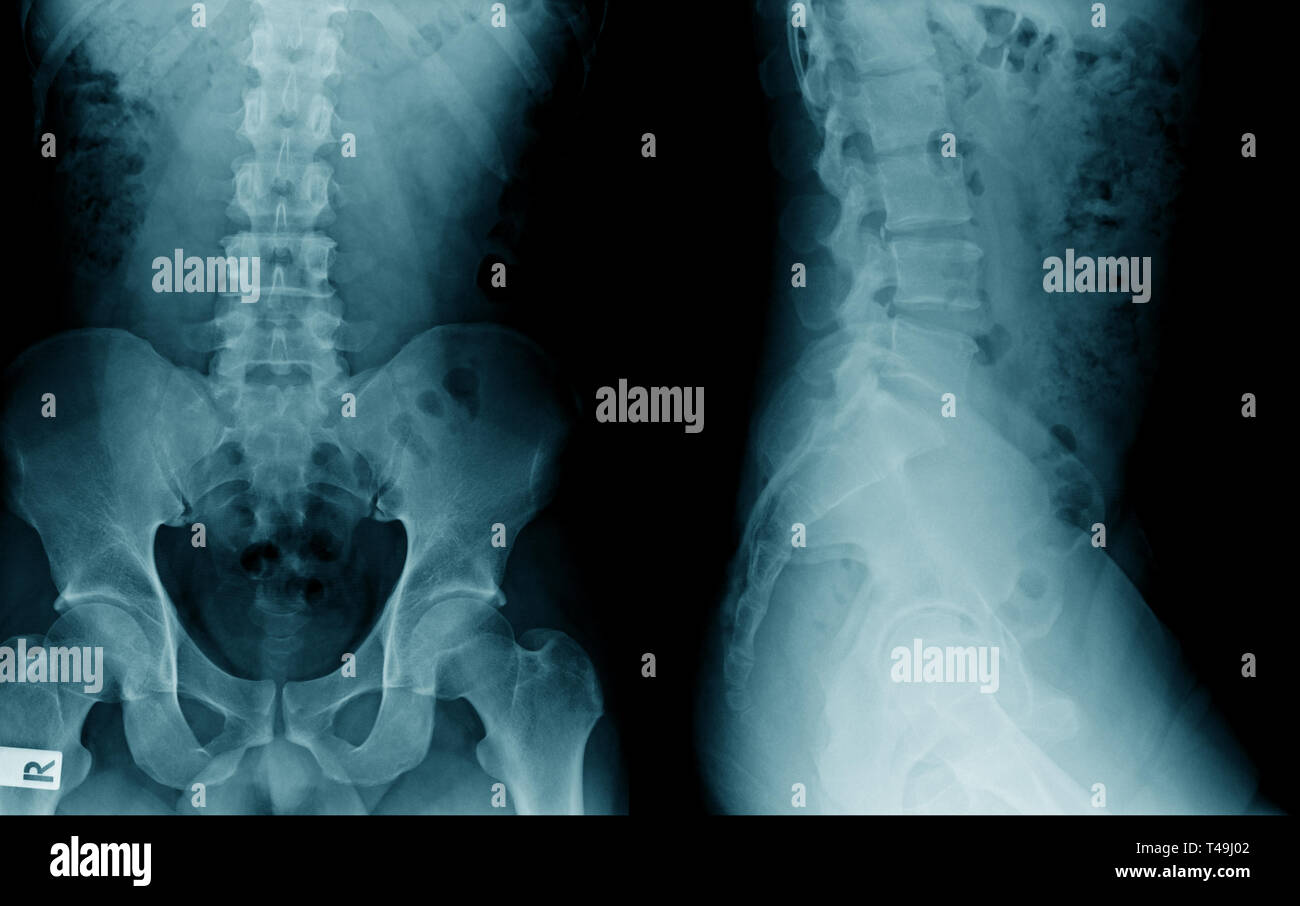

Prima di studiare una condizione patologica, bisogna conoscere a fondo la zona del corpo dove si sviluppa la malattia, nel caso della spondilosi lombare essa si verifica nella colonna vertebrale di cui bisogna conoscere la classificazione e la rispettiva funzione. La colonna vertebrale è una struttura costituita da piccole ossa, dischi e cartilagini che proteggono il midollo spinale e l'intera rete dei nervi presenti sulla parte posteriore del corpo, le ossa che si fondono e si uniscono e costituiscono la colonna vertebrale si chiamano vertebre e sono posizionate in verticale e situate una sull'altra, le vertebre si classificano in 5 regioni a seconda della posizione in cui si trovano.

La regione più alta del midollo spinale e della colonna vertebrale, che sostiene la testa e il collo, è nota come vertebre cervicali. Questa regione comprende sette ossa di piccole dimensioni che supportano la testa e il collo e ne permettono il movimento, poi ci sono le vertebre toraciche, costituite da dodici ossa che formano la gabbia toracica. La regione delle vertebre lombari è costituita da cinque ossa, questa è la regione inferiore della schiena, regge la maggior parte del peso del corpo e delle articolazioni muscolari. Le ultime due regioni sono conosciute come coda della colonna vertebrale, contengono sette ossa in tutto e sono conosciute come le vertebre sacrali e le vertebre coccigee.

La spondilosi lombare è definita come una condizione medica in cui intervengono dei disturbi nella posizione delle vertebre della colonna vertebrale. Si tratta di una condizione degenerativa che si verifica a causa dello scivolamento delle vertebre o a causa della comparsa di speroni ossei (osteofiti) tra le faccette articolari della colonna vertebrale. La spondilosi lombare, come indica il suo nome, è una malattia della colonna vertebrale lombare.

La colonna vertebrale ha 5 grandi regioni che prendono il nome di cervicale, toracico, lombare, sacrale e coccigea. La zona cervicale e la zona toracica sono le regioni superiori della colonna vertebrale, mentre la regione inferiore della colonna vertebrale inizia dalla lombare e termina al coccige (coda vertebrale).

La colonna lombare sopporta la maggior parte del peso corporeo e la maggior parte delle forze del corpo agiscono su di essa, inoltre molti muscoli del corpo sono articolati con le articolazioni della colonna lombare, sono queste le ragioni che portano alla comparsa della spondilosi, soprattutto dopo i 50 anni di età, la malattia è più comune nelle donne piuttosto che negli uomini, con l'invecchiamento le ossa si decalcificano e si indeboliscono e i pesi che si distribuiscono sulla schiena sono più difficili da sopportare.